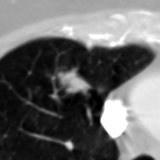

The current study focuses on lung nodule retrieval from a database of CT scans, where patches taken from CT slices of pulmonary nodules are to be mapped into an embedding. LIDC-IDRI [5] is a dataset of thoracic CT scans of 1,010 patients. All the scans were annotated by up to four radiologists, where each one identified, segmented and evaluated separately the lung nodules of a diameter above . Their evaluation also included ratings for a set of 9 characteristics: Subtlety, Internal structure, Calcification, Sphericity, Margin, Lobulation, Spiculation, Texture and Malignancy. The rating system was based on a discrete score of 1-5. Four examples of nodule patches are illustrated in Figure 2: 2 benign (a, b) and 2 malignant (c, d). A rounded vector of the mean rating is bellow each nodule, with the characteristics ordered according to the listing above. The most prominent difference between a and b is the calcification: 3 (solid) and 6 (absent) accordingly. d compared to c has a more defined margin, is more lobulated, but less spiculated. The malignancy score is used to define malignancy classes: score of 1-2 is benign, score of 3 is unknown, and a score of 4-5 is malignant.

(a) Benign

3, 1, 3, 3, 4, 3, 1, 5, 1

(b) Benign

3, 1, 6, 5, 5, 1, 1, 5, 2

(c) Malignant

5, 1, 6, 3, 3, 4, 1, 5, 5

(d) Malignant

4, 1, 6, 3, 4, 2, 2, 5, 4